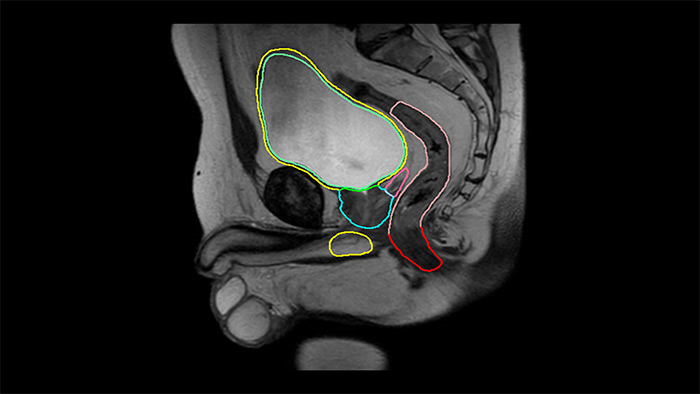

MRCAT Prostate + Auto-Contouring